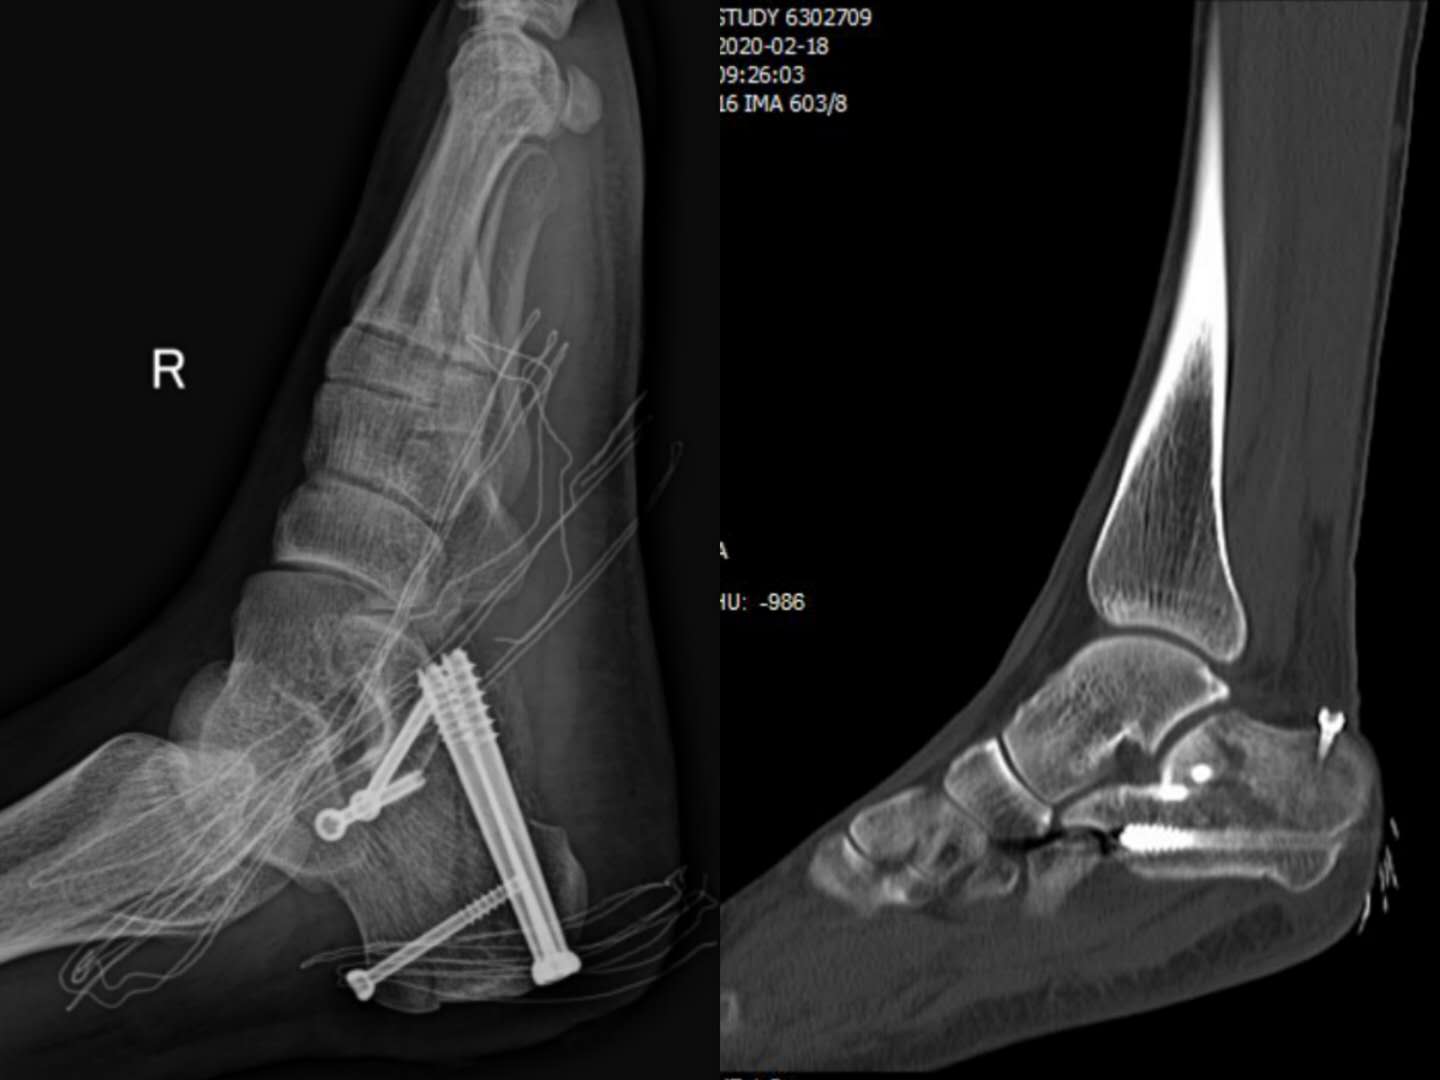

近期,兰大二院足踝外科学组副主任医师王凯在汪玉良、刘京升主任指导下,利用骨科人工智能机器人完成一例复杂跟骨骨折手术,目前该技术尚属省内首例。

患者,男,27岁,跟骨粉碎性骨折,入院时右足明显肿痛,这种情况下,传统手术需要顾及患者皮肤条件及软组织情况,待患者肿胀消退后才能行手术治疗,一般病程需两周左右,且手术效果差,对周围关节影响较大。通过人工智能机器人导航技术手术,实现了精准医疗及术后早期康复的目的,既缩短了住院时间也减轻了患者经济负担,手术效果理想。

跟骨骨折骨折类型复杂多样,手术并发症发生率高,致残率高,严重影响患者的生活。将微创理念和人工智能机器人技术结合应用于跟骨骨折,旨在减少传统手术后所出现的伤口或软组织相关并发症的发生率,又能准确复位和固定骨折。该例手术的顺利实施,标志着我院骨科在足踝及创伤领域已达到省内领先水平,至此我院骨科已在创伤、关节、脊柱、足踝等多方面同步开启了人工智能时代!